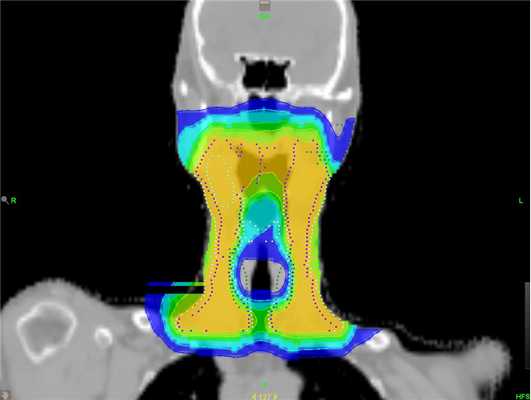

- Фотонная терапия. Именно этим видом излучения проводится лучевое лечение большинства онкологических пациентов в современном мире. Достаточно высокая проникающая способность в сочетании с высокотехнологичными способами подведения дозы (IMRT и VMAT), достаточно совершенные системы планирования позволяют очень эффективно использовать этот вид излучения для лечения пациентов с приемлемыми показателями токсичности.

Затем врач-радиотерапевт рисует объёмы облучения и критических структур (тех, на которые будет предписано ограничение дозы) на полученных срезах КТ с учётом данных других диагностических модальностей (МРТ, ПЭТ). Далее формируется задача для медицинского физика, включающая определение доз, которые должны быть подведены к мишени, мишеням или отдельным её частям, а также тех, которые не должны быть превышены в объёмах здоровых органов и тканей. Медицинский физик разрабатывает дозиметрический план в соответствии с заданными параметрами, при соблюдении которых и успешной верификации данного плана на фантоме, можно считать пациента готовым к лучевой терапии.

Использование дистанционной лучевой терапии сопровождается двумя проблемами: повреждение здоровых тканей и недостаточная регрессия новообразования. Побочные эффекты при этом иногда полностью нивелируют достигнутый результат лечения и увеличивают риск развития послеоперационных осложнений. Решить эти проблемы и увеличить эффективность радиологического лечения способна лучевая терапия с модулированной интенсивностью (IMRT), и в частности технология TomoTherapy HD.

TomoTherapy HD — комплекс, объединяющий компьютерный томограф и современный ускоритель частиц. Система позволяет точно доставить дозу радиации в опухоль какой бы сложной формы она ни была (локализовать опухоль, запланировать лечение и проводить его), оберегая от лучевой нагрузки здоровые ткани. Такой подход позволяет значительно снизить риск нежелательных проявлений.

Возможность подать дозу радиации с минимальным воздействием на здоровые ткани позволяет оказать более выраженное влияние на опухоль и снизить вероятность выраженных побочных эффектов в будущем